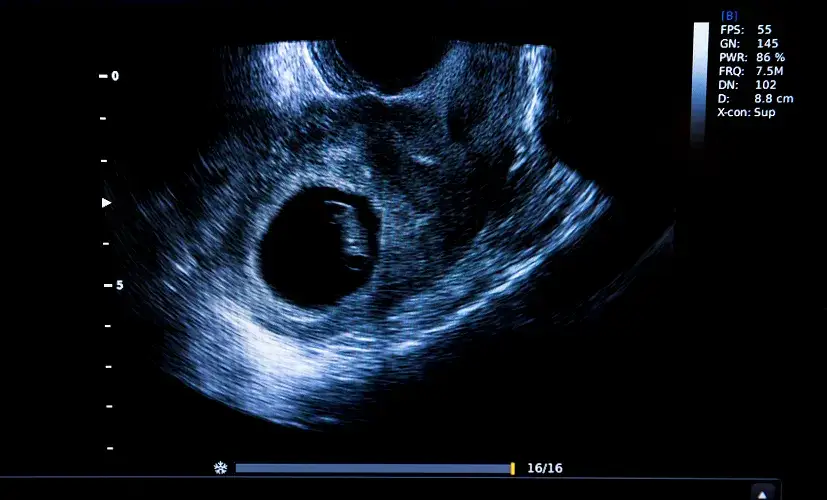

Co zobaczysz na USG w 5. tygodniu ciąży?

W 5. tygodniu ciąży obraz USG jest jeszcze bardzo subtelny, ale już wtedy możemy dostrzec kluczowe struktury, które potwierdzają prawidłowy rozwój. To, co zobaczycie na monitorze, będzie zależało od dokładnego dnia w tygodniu, jakości sprzętu i doświadczenia lekarza.

Pęcherzyk ciążowy: Pierwszy pewny dowód ciąży

Pierwszą i najważniejszą strukturą, którą lekarz będzie szukał w macicy, jest pęcherzyk ciążowy (GS). To on jest pierwszym pewnym dowodem na to, że doszło do zagnieżdżenia ciąży. Na USG pęcherzyk ciążowy wygląda jak mały, ciemny, okrągły lub owalny obszar wewnątrz macicy. Jego obecność jest kluczowa, ponieważ potwierdza prawidłowe zagnieżdżenie ciąży w jamie macicy, co pozwala wykluczyć ciążę pozamaciczną. Na początku 5. tygodnia pęcherzyk ma średnicę około 3-5 mm, a pod koniec tygodnia może osiągnąć nawet 11 mm. Przyrasta średnio o 1-1,3 mm na dobę, co jest ważnym wskaźnikiem prawidłowego rozwoju.

Pęcherzyk żółtkowy: Mały bohater wielkiej zmiany

Wewnątrz pęcherzyka ciążowego, często już w 5. tygodniu, można dostrzec kolejną niezwykle ważną strukturę pęcherzyk żółtkowy (YS). Jest to mniejsza, regularna, jasna, okrągła struktura. Jego widoczność to bardzo dobry znak, ponieważ potwierdza prawidłowy rozwój wczesnej ciąży. Pęcherzyk żółtkowy pełni niezwykle istotną rolę odpowiada za odżywianie zarodka do czasu, aż wykształci się łożysko i przejmie tę funkcję. To taki mały, tymczasowy bohater, który dba o pierwsze potrzeby rozwijającego się życia.

- GS (Gestational Sac) Pęcherzyk ciążowy: To pierwsza struktura widoczna w macicy, która potwierdza, że ciąża zagnieździła się prawidłowo. Wygląda jak mały, ciemny, okrągły lub owalny obszar.

- YS (Yolk Sac) Pęcherzyk żółtkowy: Mniejsza, jasna, okrągła struktura wewnątrz pęcherzyka ciążowego. Jest to bardzo dobry znak, świadczący o prawidłowym rozwoju wczesnej ciąży i odpowiada za odżywianie zarodka.